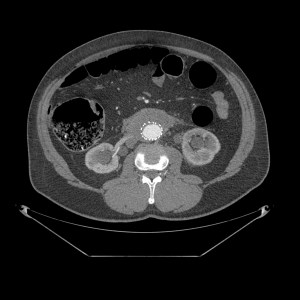

Paciente con aneurisma de aorta con dolor abdominal difuso y bilateral. Sin otros hallazgos clínicos y ni analíticos. Constantes vitales estables.

El TC abdominal en fase portal y excretora evidencian una masa que compromete ambos uréteres, más acentuada a la izquierda, produce hidronefrosis bilateral, hallazgo muy infrecuente en el linfoma. Además es isodenso con respecto al músculo, rodea la aorta por la parte anterior, no la desplaza hacia adelante y está en situación infrarrenal predominantemente. No hay adenopatías. Solución: estamos ante una Fibrosis Retroperitoneal.